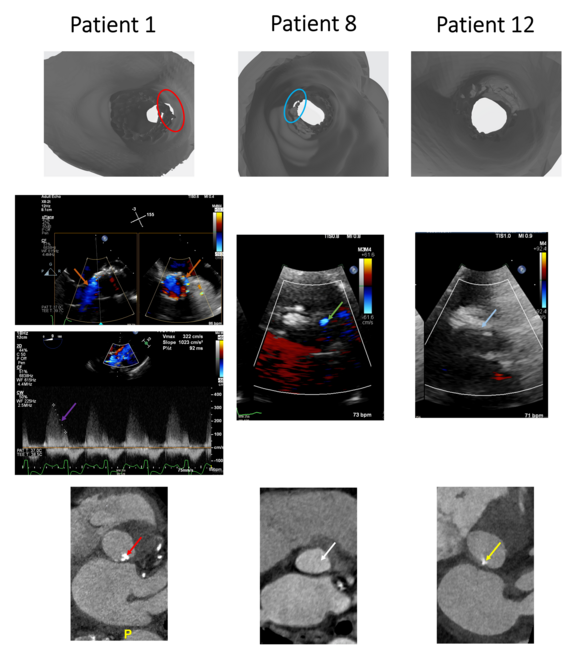

Figure 1 features 3 patient scenarios. Patient 1 had a 25% malapposition in VR-TAVR and was found to have a moderate PVL. His cardiac CT prior to TAVR showed moderate annular calcification. Patient 8 had an approximately 10% malapposition and was found to have mild PVL. He had no annular calcification. Patient 12 had no malapposition, no PVL, and mild annular calcification.

There were other adverse events noted in our patient population directly related to pre-procedure planning and sizing. In patient 1 (Sievers type 0), there was no significant valve oversizing based on VR-TAVR, and moderate annular calcification was present (Table 3). After valve implantation, a moderate PVL was noticed on transesophageal echocardiography. Post-dilation, PVL did not resolve with a 23-mm balloon, and another 26-mm Edwards Sapien valve was implanted 3 mm lower in the left ventricular outflow tract (LVOT). This was complicated by annular rupture, cardiac arrest, and death in the immediate post-procedural period. In patient 16 (Sievers type 0), 3 days after successful placement of a 23-mm Edwards Sapien valve, the valve dislodged with a significant degree of stenosis and required urgent SAVR with a 21-mm St Jude Trifecta tissue valve. Patient 12 (Sievers type 1) had significant annular calcification at the right coronary cusp level and developed a ventricular septal defect post-procedure. The TAVR valve in patient 9 (Sievers type 0) did not expand completely and had 7% oversizing based on VR-TAVR, although only mild annular calcification was present. Patient 15 (Sievers type 1) had a low implant (-1.2% oversizing based on VR-TAVR). Patient 8 (Sievers type 0) developed mild PVL. Patient 2 (Sievers type 1) had an annular area of 7.5 cm2, annular perimeter of 95.6 mm, 10% malapposition, and a mild PVL even with a 34-mm Evolut valve.